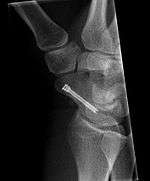

The scaphoid can be slow to heal because of the limited circulation to the bone. Fractures of the scaphoid must be recognized and treated quickly, as prompt treatment by immobilization or surgical fixation increases the likelihood of the bone healing in anatomic alignment, thus avoiding mal-union or non-union. Delays may compromise healing. Failure of the fracture to heal ("non-union") will lead to post-traumatic osteoarthritis of the carpus.[1] :189 One reason for this is because of the "tenuous" blood supply to the proximal segment.[2] Even rapidly immobilized fractures may require surgical treatment, including use of a headless compression screw such as the Herbert screw to bind the two halves together.

Healing of the fracture with a non-anatomic deformity (frequently, a volar flexed "humpback") can also lead to post-traumatic arthritis. Non-unions can result in loss of blood supply to the proximal pole, which can result in avascular necrosis of the proximal segment.